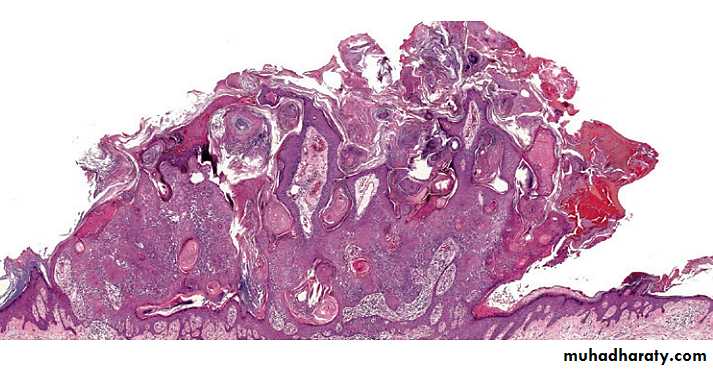

HP of SKs

There are at least six histologic types of SK but different histologic features are often present in the same lesion:• Acanthotic: the most common.

• Hyperkeratotic: more prominent hyperkeratosis and papillomatosis.

• Reticulated: delicate strands of epithelium that extend from the epidermis in an interlacing pattern.

• Irritated: perivascular, diffuse or lichenoid lymphoid infiltrate. Squamous eddies are common findings.

• Clonal: well defined nests of loosely packed uniform cells in the epithelium.

• Melanoacanthoma: shows dendritic melanocytes packed with melanin which is absent in keratinocytes.

HP of SKs The acanthotic type

Usually presents as a smooth surfaced, dome shaped papule. Slight hyperkeratosis and papillomatosis are often present, while the greatly thickened epidermis typically contains a preponderance of basaloid cells.Sharply demarcated horizontal base called “string”.

Papillae may be narrow in some lesions.

Invaginated horn pseudocysts are most prevalent in this variant.

This type often contains an amount of pigment superior in quantity than others; it is primarily concentrated in keratinocytes and is transferred from neighboring melanocytes and deeply pigmented lesions contain abundant melanin in basaloid cells.

Acanthotic type

with church spires of papillomatosis and hyperkeratosis & preponderance of squamous cells relative to basaloid cellsHyperkeratotic type

with delicate, lace-like strands of interconnecting epithelium composed of a double row or more of hyperpigmented basaloid cells and interspersed horn pseudocysts

Reticulated type

exophytic lesion with papillomatosis, hyperkeratosis, hemorrhagic crust and dermal inflammation

Irritated type

with Borst–Jadassohn phenomenon* characterized by well-demarcated nests of keratinocytes within the epidermis

Clonal type

* ‘clones’ of basaloid, squamatized, or pale keratinocytes in epidermis appear different than their neighbors